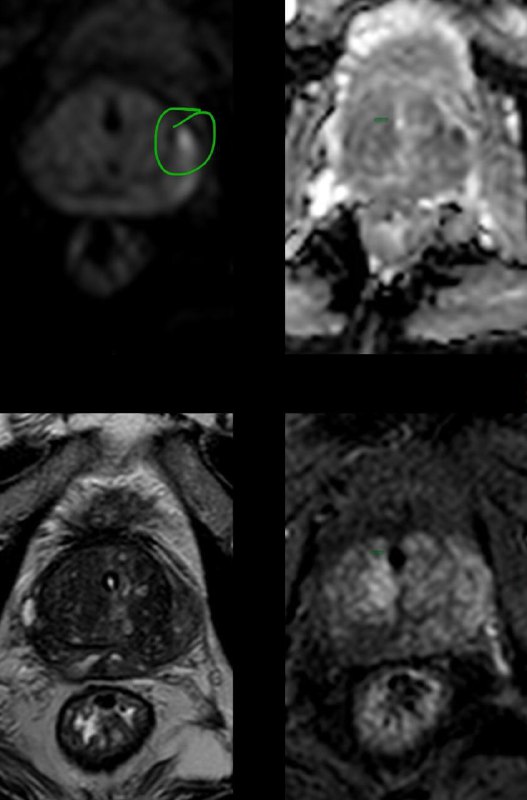

Дивертикул матки у женщины 45 лет.

Дивертикул матки - это редкий врожденный порок развития, вызванный аномальным слиянием мюллеровых протоков.

Диагноз дивертикула матки затруднен, и его часто неправильно диагностируют как другую аномалию Мюллерова протока (например, кровь в рудиментарном роге матки), миому матки с дегенерацией, эндометриому или геморрагическую кисту яичника.

Встречается так редко, что я, вот, первый раз сам увидел, и то, спасибо коллеге из Алма-Аты.